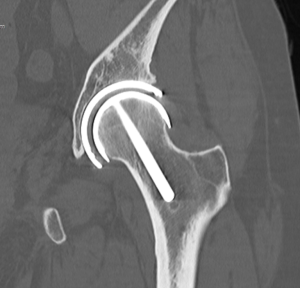

Methods

Bone retention

Figure 5 shows the bone retention and absence of acetabular wear 11 years following an entirely cementless hip resurfacing arthroplasty. The results of bone retention evaluation have been reported previously (32). Briefly, the mean acetabular wall was 10 mm thick postoperatively vs. 15 mm preoperatively, the head: neck ratio was 1.36 postoperatively compared to 1.42 preoperatively. The leg length increased a mean of 4 mm postoperatively. The acetabular component was a mean of 3.9 mm to Kohler’s line and there were no instances of compromise to the femoral neck or medial wall.